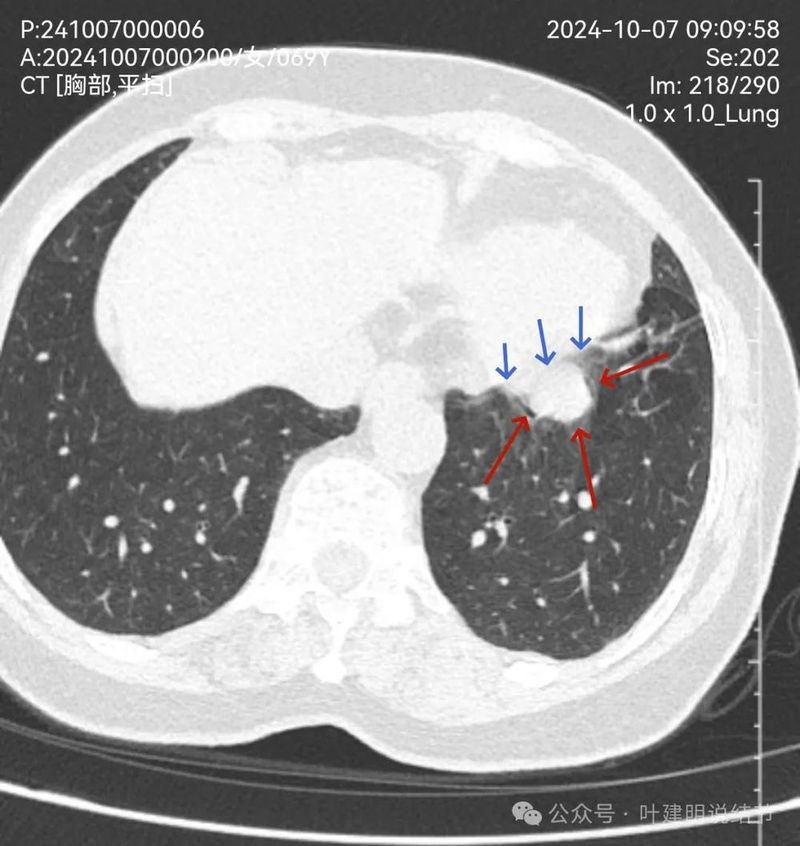

右上混合密度结节,有血管进入,有实性成分,磨玻璃部分轮廓与边界清,与恶性较为符合,浸润性腺癌可能性较大点。当然由于首次发现,先抗炎后再复查更为稳妥些,有时炎性也会边界较清的。

左上叶磨玻璃结节,密度稍不均,有部分偏实性成分,表面不平,轮廓与边界清,似有微小血管进入,恶性范畴的可能性大些。

右上叶磨玻璃结节,轮廓清,表面不平,不典型增生或原位癌可能性大。

右中叶条索状病灶,考虑慢性炎或纤维条索;

右下叶胸膜下微小磨玻璃结节,有微血管征,轮廓与边界清,不典型增生可能性较大。

右下叶囊腔型病灶,囊壁较薄,内部有分隔,囊腔型肺癌不能完全除外,但肯定要先随访起。

右下另处囊腔灶,灶内有血管穿过,整体小且囊壁薄,再观察下。